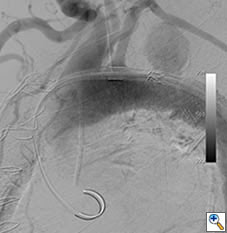

The patient underwent repeat CTA 1 month later which demonstrated thrombosis of the false lumen except for a 4.5 x 4.6cm pseudoaneurysm proximal to the distal repair. (Figure 4) Since the new finding appeared to have a defined neck, the possibility of an endovascular exclusion of the fenestration was discussed with the back-up plan being either open or hybrid arch replacement. The patient underwent a carotid subclavian bypass using an 8mm Gore-Tex ring graft (WL Gore & Associates Inc, Flagstaff, AR) to extend the proximal landing zone. Aortic coverage was planned from the combined origin of the brachiocephalic and left common carotid arteries (bovine arch anatomy) down into the previously placed tube graft. Two days later, two Cook TX2 thoracic endografts (Cook Inc, Bloomington, IN) 30 x 120mm and 36 x 127mm were overlapped to exclude the intimal defect. Completion angiography demonstrated contrast in the proximal subclavian without perfusion of the false lumen. (Figure 5)

Figure 5a. Intraoperative angiogram demonstrating 4.4 x 4.6cm pseudoaneurysm distal to the left subclavian artery.

Figure 5b. Angiography after carotid-subclavian bypass and exclusion of pseudoaneurysm with a Cook TX2 thoracic graft. Note bovine arch anatomy with combined origin of brachiocephalic and carotid arteries.